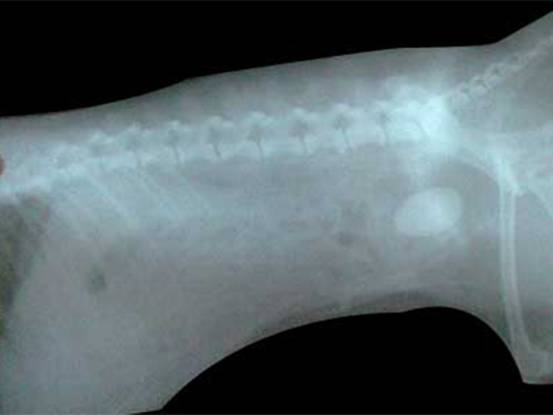

图3:X光片显示该猫膀胱内有结石